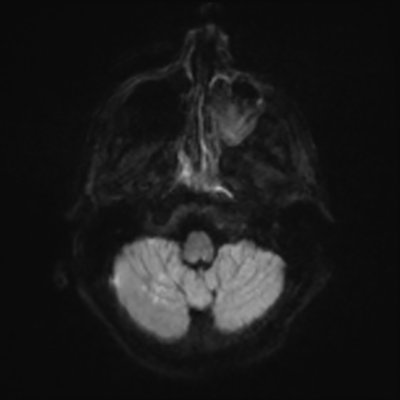

MRI brain (DWI)

You can clearly see diffuse cortical and basal ganglia diffusion restriction, and that of his deep cerebellar nuclei as well. The right occipital lobe abnormalities are a little more prominent, but then you remember that he is known to have had a right occipital stroke weeks ago.